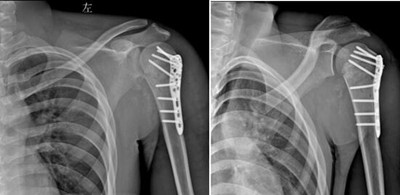

完善术前相关准备后,骨科王延斌主任及其团队为患者进行“左肱骨近端骨折切开复位内固定术”,术后DR显示内固定良好。

术后DR